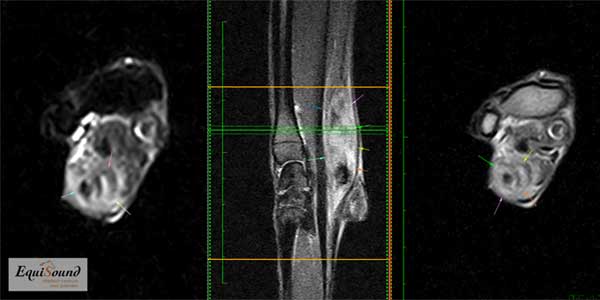

Het diagnosticeren van peesblessures gebeurt reeds 30-40 jaar aan de hand van een echografisch onderzoek. Deze diagnostische techniek is zeer geschikt op plaatsen waar de pezen oppervlakkig liggen. Voor diepere structuren zoals de bovenste aanhechting van de interosseus en de diepe buigpees in de voet bij het paard is een MRI scan de "technique of choice" om blessures en degeneratieve haarden goed in beeld te brengen. Ook toont de MRI-scan contrastrijk de actieve zones in de pees. (foto 3-7)

MRI beelden (vlnr T1 transversaal, T1 sagittaal) van een paard met een opspelende chronisch degeneratieve insertiedesmopathie. Behalve de verdikking van de mediale lobe met het verhoogd T1 signaal aan de dorsale zijde (fibrosering), zijn er bij dit paard duidelijke tekenen van chronicteit in de palmaire cortex van het pijpbeen: een defect aan de palmaire zijde ten gevolge van chronische druk en een intramedullaire sclerose van de dorsale zijde.